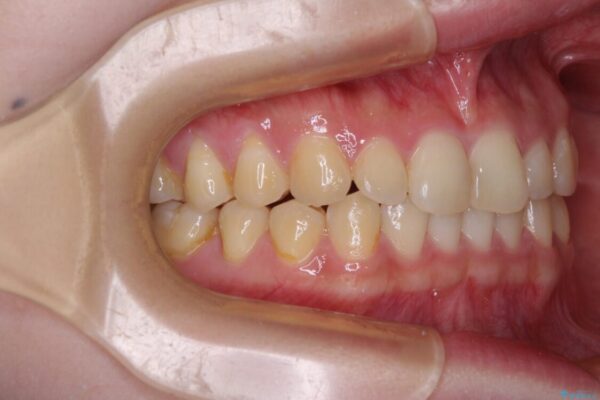

根管治療を行ったままの奥歯と、矯正治療の後戻りを気にして来院された患者様です。

矯正治療の後戻りは軽微であったため、インビザラインの簡易パッケージであるインビザライン・ライトを用いて歯列を整えることとしました。

治療前

• 治療途中の奥歯と矯正治療の後戻り インビザライン・ライトによる矯正治療 治療前画像